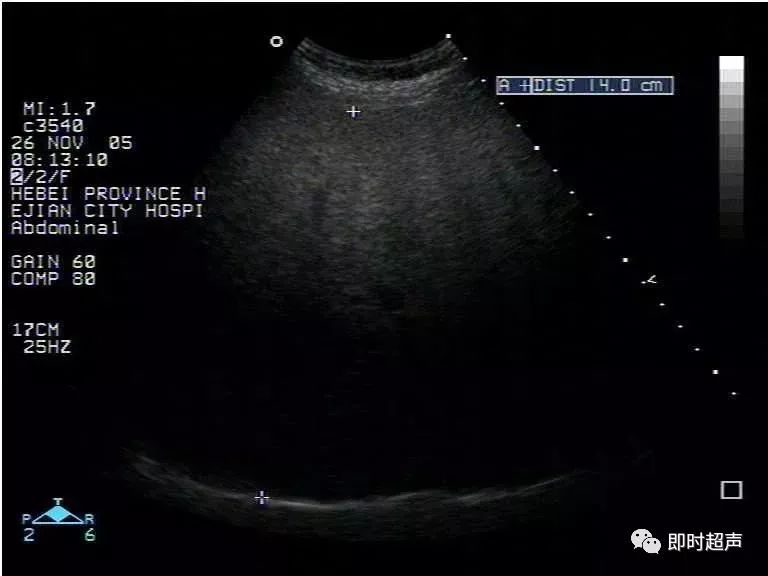

超声表现:

1、肝实质回声细密增强,呈云雾状,后方回声衰减。

2、肝内管道结构显示欠清。

3、肝肾对比阳性,正常情况下肝脏回声略高于肾实质回声,脂肪肝时肝脏回声明显增强。

4、肝脏增大,形态饱满,边缘变钝。

脂肪肝的分度

根据肝脏回声,肝内管道及膈肌显示情况可对脂肪肝进行分度。

轻度:肝回声增强,后方回声衰减不明显,肝内管道结构显示正常。

中度:肝回声明显增强,后方回声衰减,肝内管道结构显示欠清晰。

重度:后方回声衰减明显,后方肝组织显示不清,膈肌显示不清。